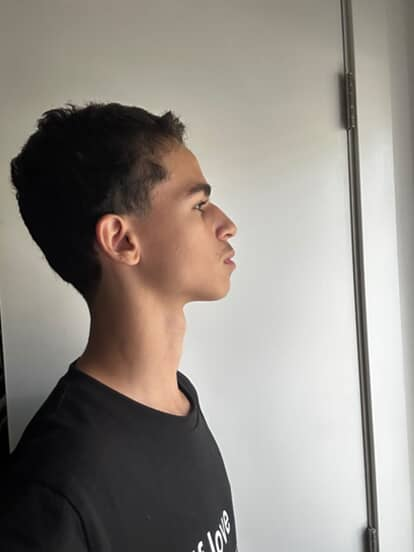

View attachment 4232105 Thoughts on the treatment plan my ortho gave me i just wanna fix my convex profile that i developed thru bad habits is their any diy thing i can do + any advice for my coloring etc

View attachment 4232105 Thoughts on the treatment plan my ortho gave me i just wanna fix my convex profile that i developed thru bad habits is their any diy thing i can do + any advice for my coloring etc

View attachment 4232105 Thoughts on the treatment plan my ortho gave me i just wanna fix my convex profile that i developed thru bad habits is their any diy thing i can do + any advice for my coloring etc

View attachment 4232105 Thoughts on the treatment plan my ortho gave me i just wanna fix my convex profile that i developed thru bad habits is their any diy thing i can do + any advice for my coloring etc

View attachment 4232105 Thoughts on the treatment plan my ortho gave me i just wanna fix my convex profile that i developed thru bad habits is their any diy thing i can do + any advice for my coloring etc

View attachment 4232105 Thoughts on the treatment plan my ortho gave me i just wanna fix my convex profile that i developed thru bad habits is their any diy thing i can do + any advice for my coloring etc